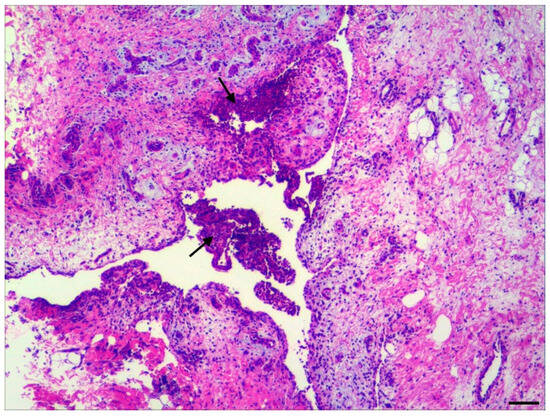

3.2. Histopathology

3.3. Bacteriology of Joint and Meningeal Swabs